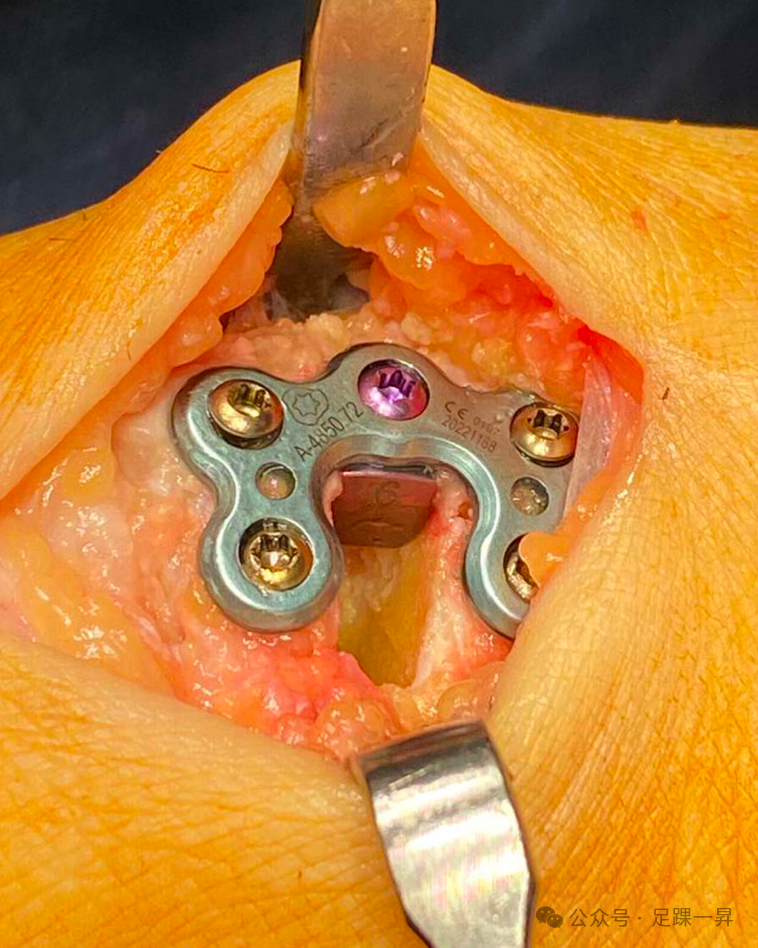

高弓足顾名思义指的是侧面观足弓高企,在行走或者负重过程中过程失去弹性,不能相对变平,从而不能完成正常站立和行走功能。